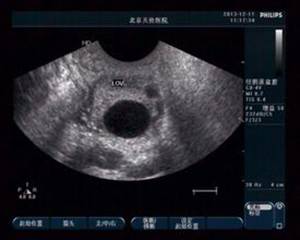

(圖:超聲示未破裂的卵泡)

1、陰道超聲:我們對LUFS的診斷,一般是根據自然周期LH峰值,或HCG注射48h后卵泡仍然沒有塌陷或消失的超聲影像來做出的。由于有時排卵后卵泡壁塌陷的超聲征象并不典型,或排卵后的卵泡有時也并不塌陷,在外觀上也難以判斷,因此僅憑超聲圖像診斷可能有一定的局限性。